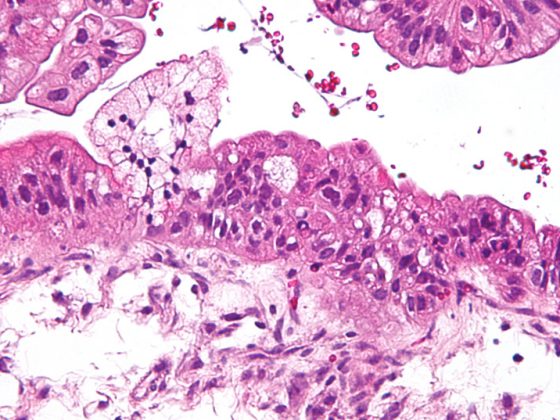

Como resultado de la remodelación, la DBP se caracteriza por una disposición patológica de la elastina y cambios cualitativos y cuantitativos en el entramado de colágeno. [108–110] Caracteriza la función estructurante de la matriz como andamiaje para la formación de nuevos alvéolos y capilares y define el destino de las células que pueblan el órgano en desarrollo. [111,112] (Fig. 2). La reorganización irreversible de la matriz extracelular provocará así cambios a largo plazo que se manifestarán a varios niveles.

Los cambios histopatológicos y el desarrollo y aspecto clínicamente heterogéneos de la DBP sugieren la existencia de (sub)entidades de la enfermedad o, al menos, una influencia individualmente diferente de los diversos cambios estructurales en el aspecto clínico y el curso a largo plazo. En este contexto, la presencia de procesos primarios enfisematosos o de remodelación intersticial, cambios vasculares y/o patologías del tracto respiratorio son “variables” presumiblemente indicativas de DBP, que en estudios iniciales también pueden representarse morfológicamente por imagen en los bebés prematuros mediante estrategias de imagen clínicamente factibles [113–117]. Mediante la reproducción de estudios realizados con éxito en otras áreas patológicas, el uso de otras estrategias de diagnóstico por imagen [118–121] podría mejorar aún más la estratificación de los pacientes en el futuro.